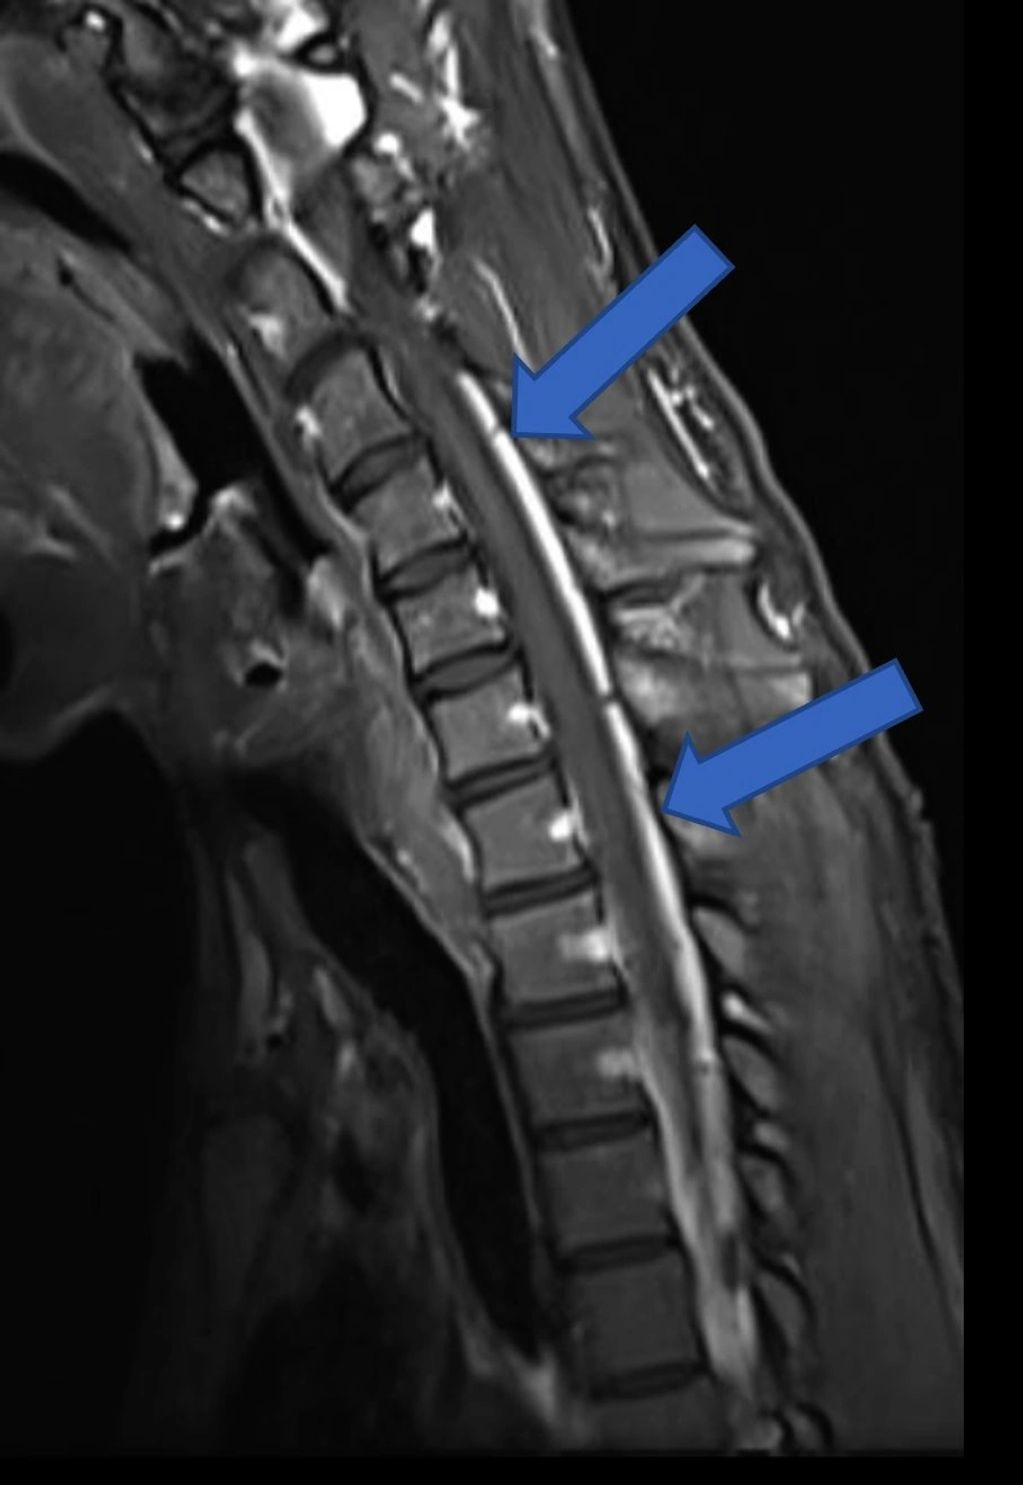

Neutral position: Sagittal T2 MRI of cervical spine showing normal canal dimensions

Flexion MRI: Sagittal T2 weighted image of cervical spine showing posterior dural laxity/increase in laminodural space with flattening of the cord

Flexion MRI: Post-contrast sagittal MRI showing enhancement of the epidural space